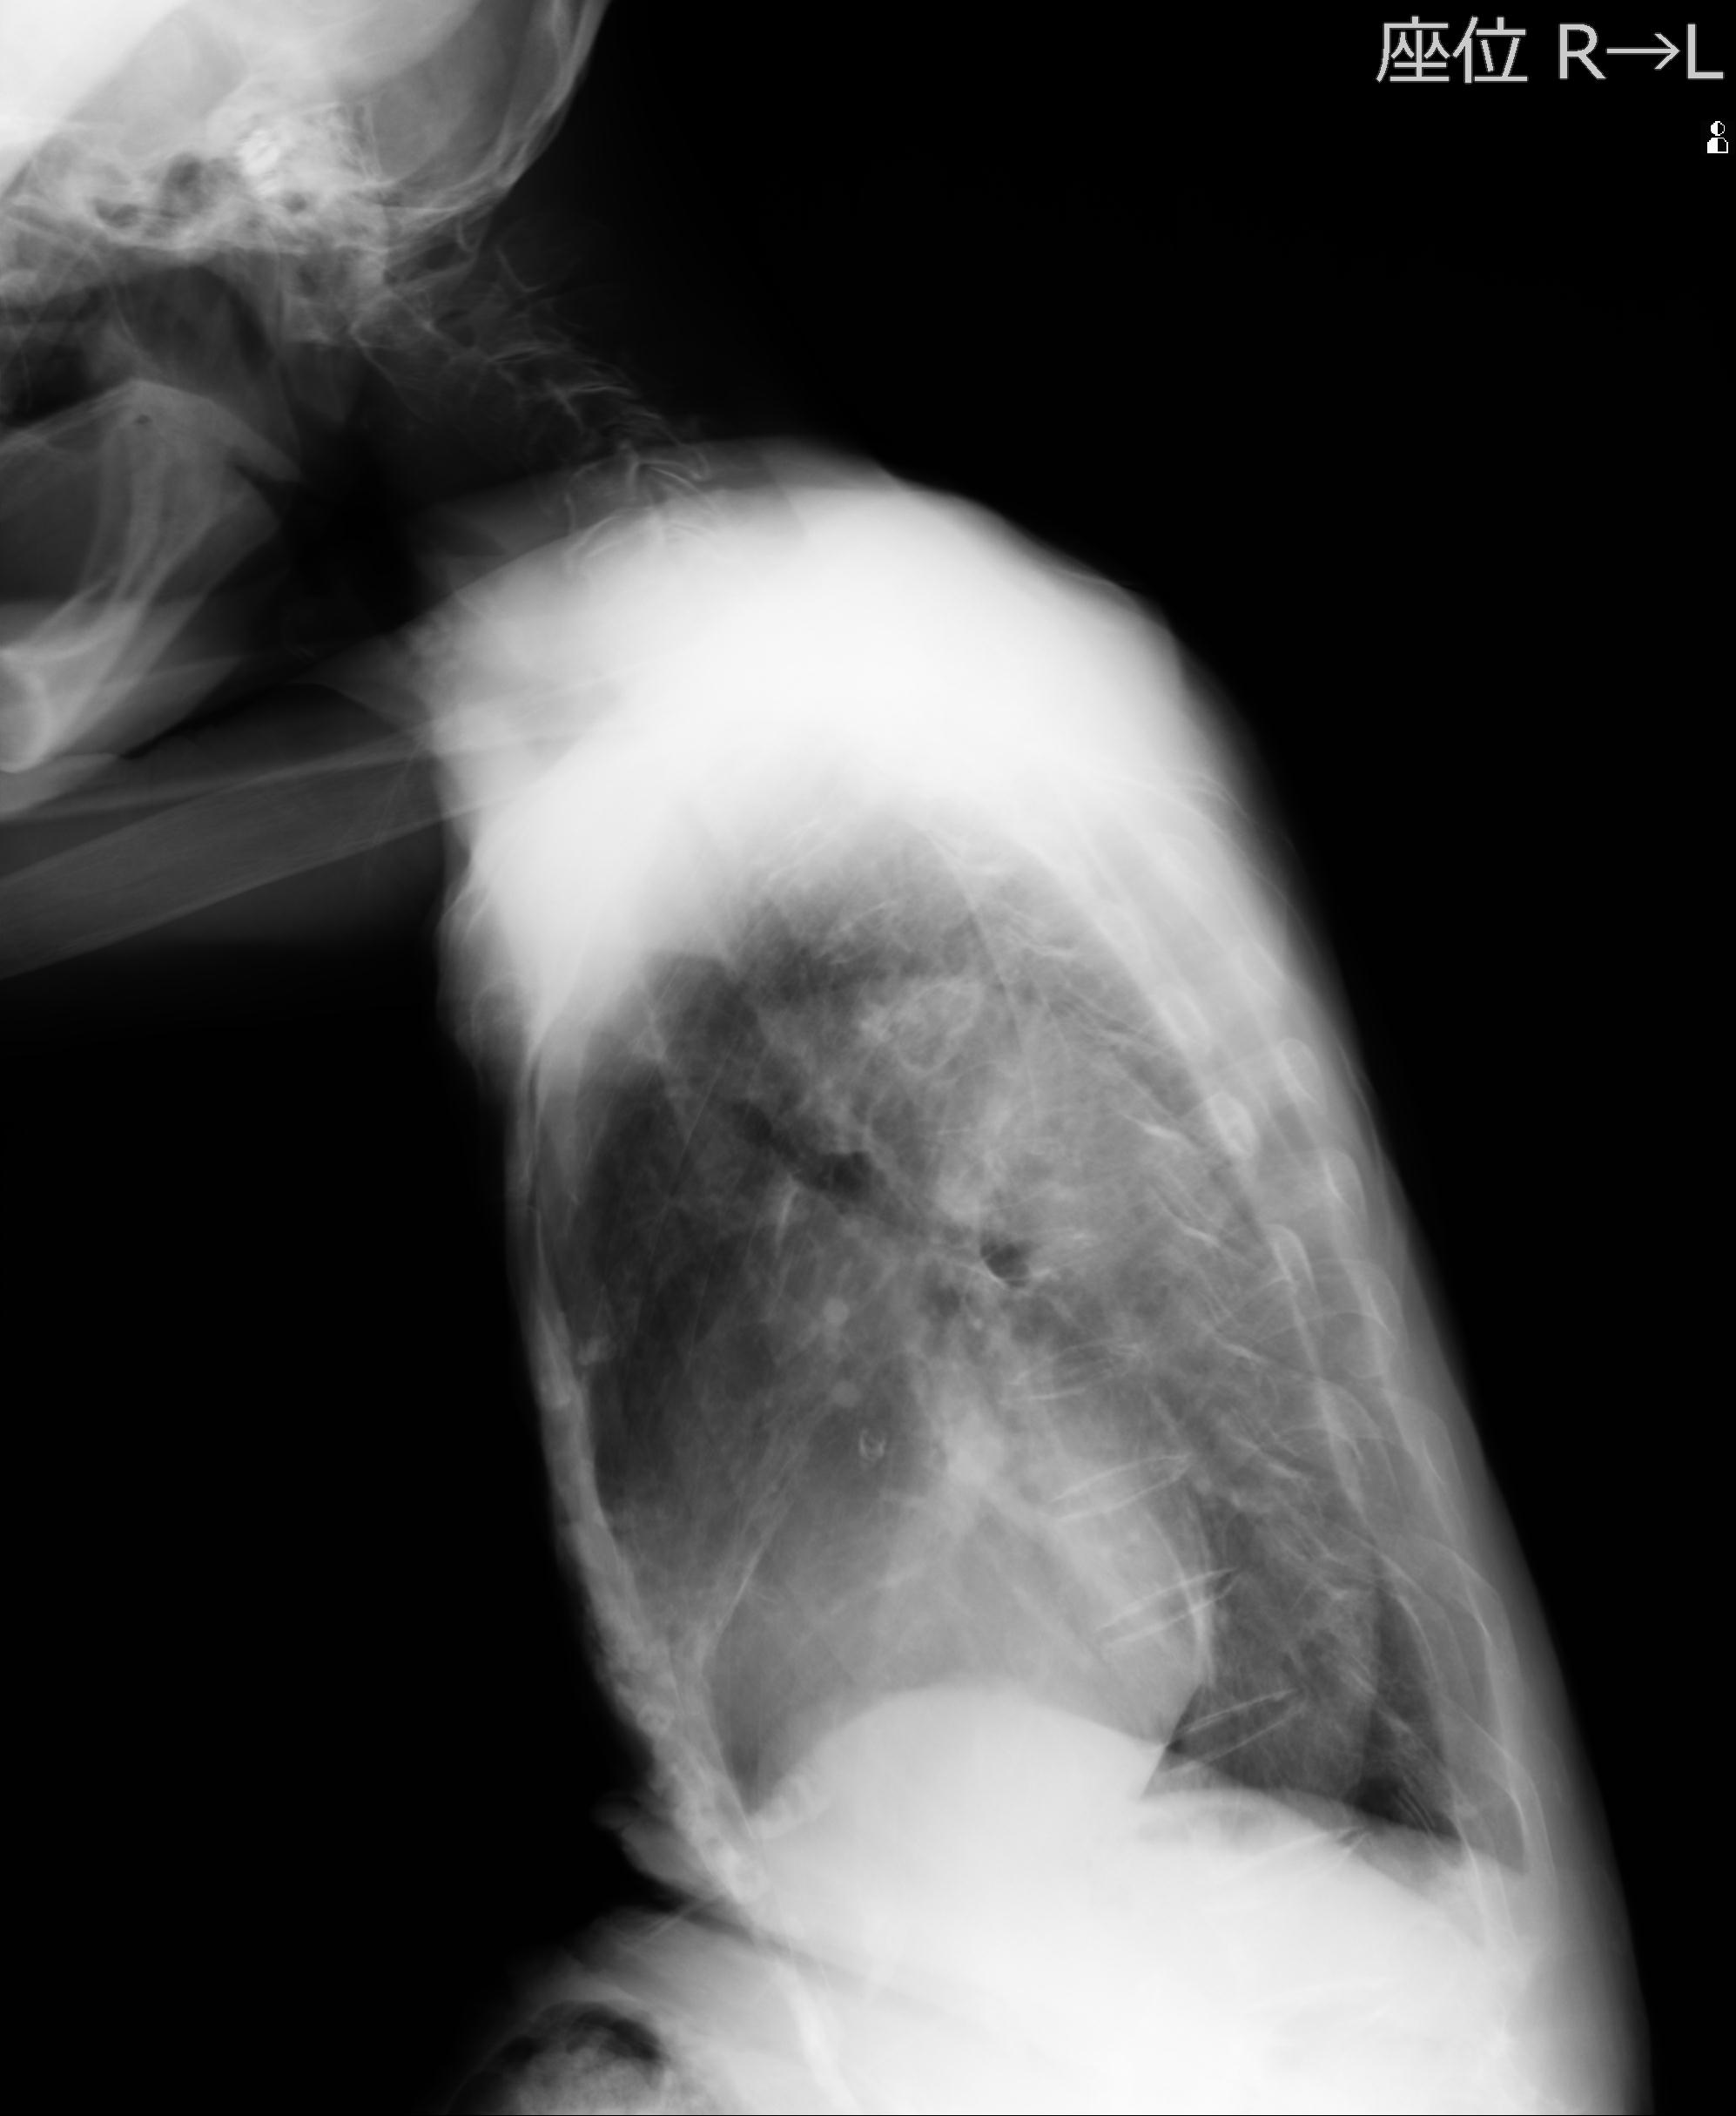

110214 12/20 肩 2R 12/21 肩 4R 72歳女性 左上腕外科頚プレート